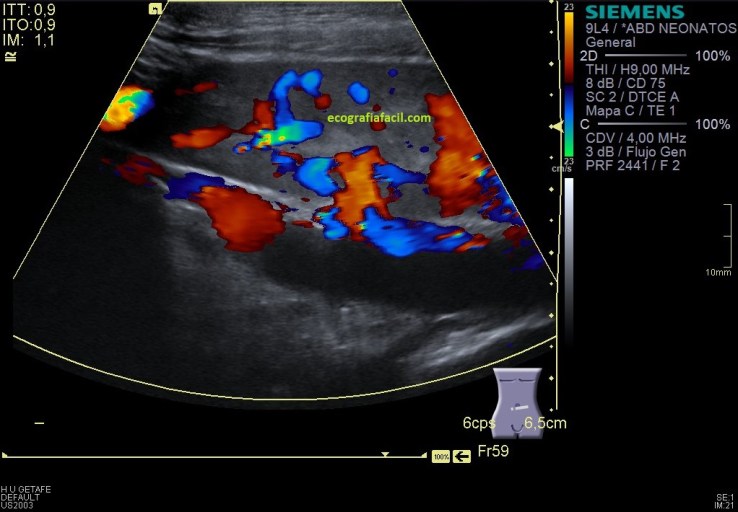

Las imágenes 12,13 y 14 son el doppler y el doppler pulsado del riñón izquierdo, que aunque malrotado y ectópico mantiene un aspecto normal tanto en modo B, como en el doppler color y en el modo angio o doppler power. El espectro es normal, con valores de aceleración superiores a 300 cms/sg.